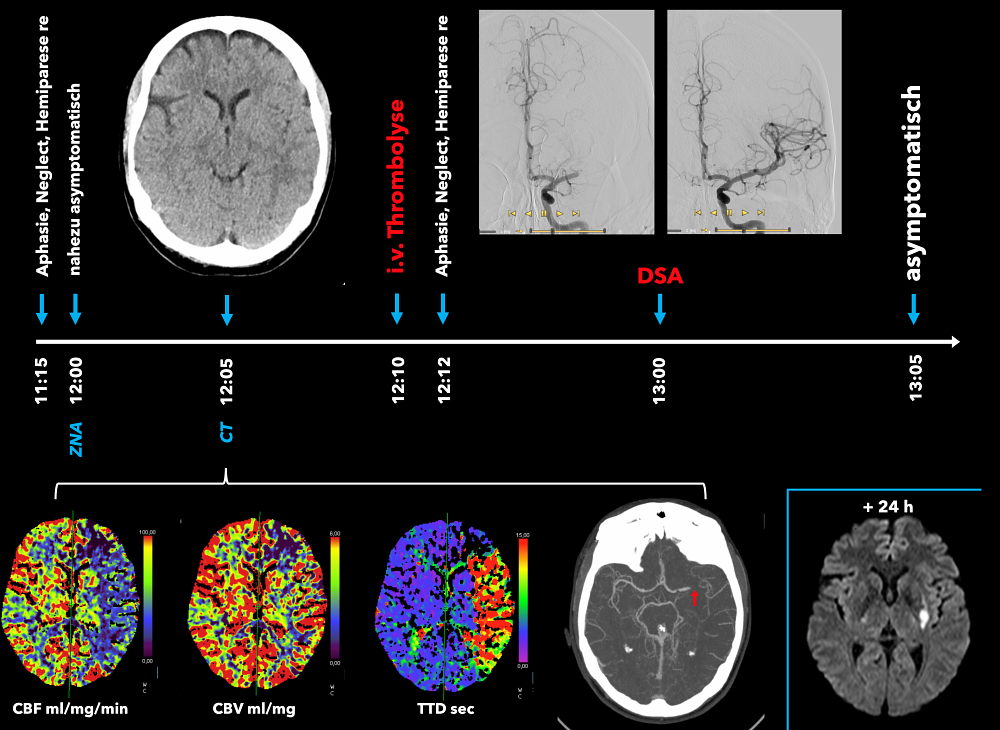

Abbildung 2

Abbildung 2: Eine 33-jährige Patientin erleidet um 11:15 Uhr zu Hause einen schweren Schlaganfall mit Aphasie und einer Hemiparese rechts. Die Patientin wird durch den alarmierten Rettungsdienst in der Zentralen Notaufnahme vorgestellt. Zu diesem Zeitpunkt ist die Patientin wieder nahezu asymptomatisch. Das multimodale CT (natives CT, CT-Angiographie und CT-Perfusion) zeigt ein unauffälliges Parenchym, einen Verschluss der A. cerebri media im Hauptstamm links und ein Mismatch in der Perfusion linkshemisphärisch. Trotz nahezu asymptomatischer Patientin erfolgt aufgrund der diagnostischen Befunde eine intravenöse Thrombolyse, gleichzeitig wird die Patientin einer endovaskulären Thrombektomie durch die Neuroradiologie zugeführt. In der Zwischenzeit entwickelt die Patientin erneut schwere Schlaganfallsymptome; dies weist auf eine instabile Perfusionssituation hin. Wenige Minuten nach der Rekanalisation ist die Patientin wieder asymptomatisch. Im späteren kranialen MRT zeigt sich in der diffusionsgewichteten Sequenz (DWI) lediglich eine kleine Restriktion in den Stammganglien links. In der Folge wird die Patientin ohne Defizite entlassen.